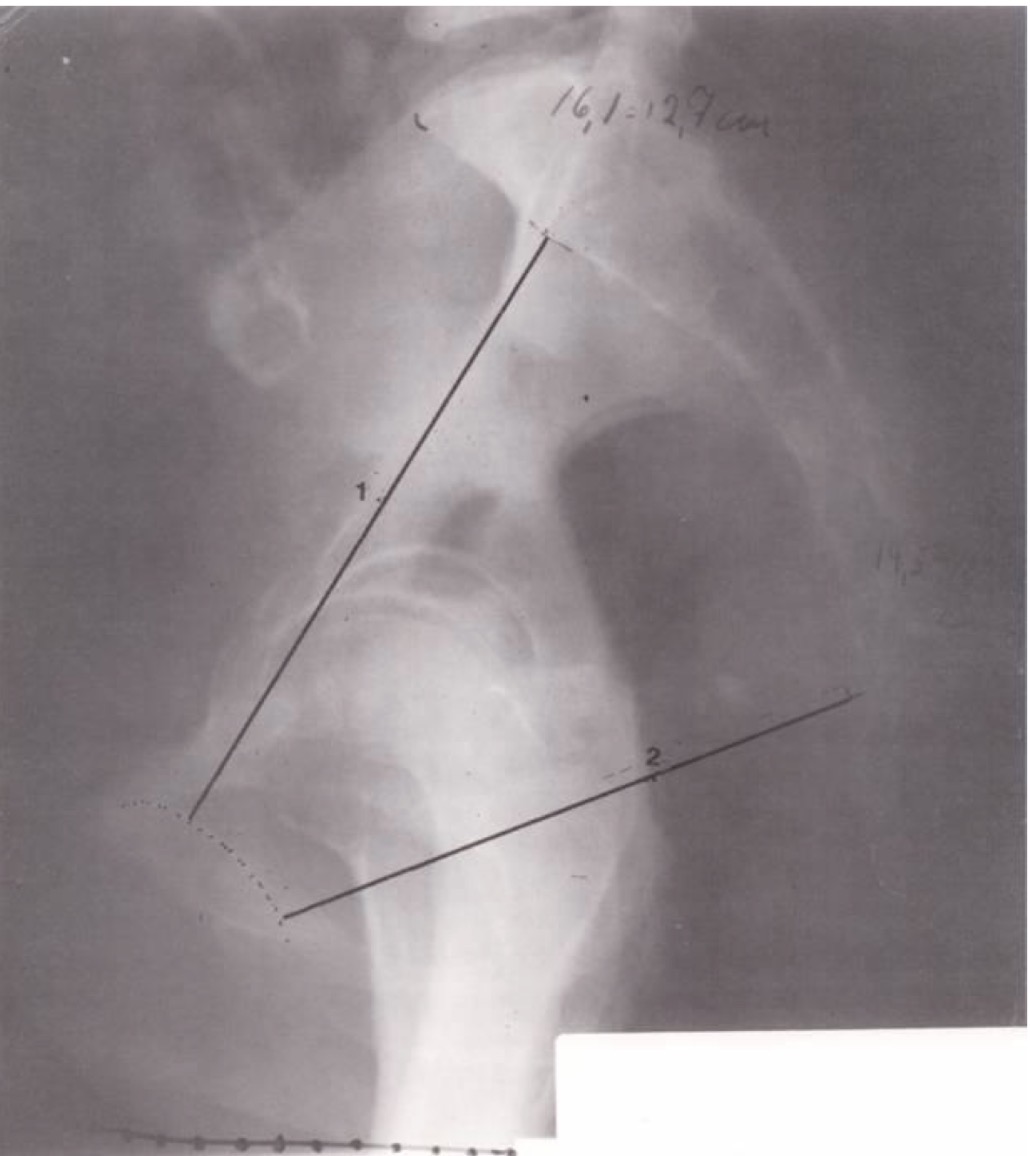

1

Sagitalinis įėjimo į mažąjį dubenį diametras (trumpiausias atstumas tarp symphysis pubica vidinio paviršiaus ir kryžkaulio viršutinės dalies; normali vertė >11 cm)

2

Sagitalinis išėjimo iš mažojo dubens matmuo (trumpiausias atstumas nuo sąvaržos iki kryžkaulio viršūnės)

Nr. 3. Tyrimas atliktas pacientei gulint ant šono. Tarp kojų įdėta metalinė liniuotė masteliui patikslinti (graduotas šešėlis).

Pastaba apie kyšulį

Kyšulį (promontorium) suformuoja labiausiai atsikišęs į priekį S1 slankstelio kūno viršutinio krašto taškas. Matuojant išėjimo matmenį, į stuburgalį galima neatsižvelgti, nes jis gimdymo metu pasislenka.